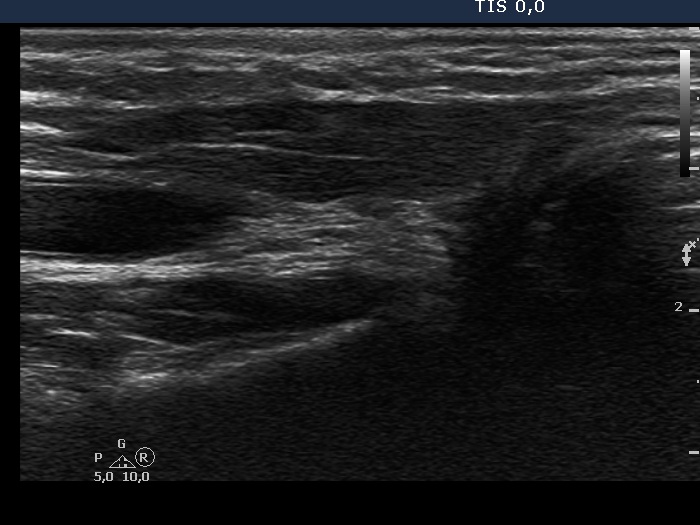

Clinical data: A 41-year-old woman was referred for follow-up examination. She underwent total thyroidectomy and radioiodine therapy for 5 years because of papillary carcinoma. She had no complaints.

Result of blood test: euthyroidism on daily 175 microgram levothyroxine (TSH 0.33 mIU/L).

Ultrasonography. There was no parenchyma according to the thyroid lobes. Connective tissue and muscle fiber have replaced the thyroid tissue, dorsal and ventral part, respectively.